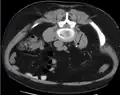

In people with a history of stones, those who are less than 50 years of age and are presenting with the symptoms of stones without any concerning signs do not require helical CT scan imaging.[63] A CT scan is also not typically recommended in children.[64]

Otherwise a noncontrast helical CT scan with 5 millimeters (0.2 in) sections is the diagnostic method to use to detect kidney stones and confirm the diagnosis of kidney stone disease.[16][56][60][65][7] Near all stones are detectable on CT scans with the exception of those composed of certain drug residues in the urine,[58] such as from indinavir.